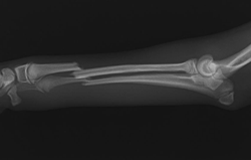

■ 症例1

小型犬の橈尺骨骨折

ロッキングプレート(TITAN LOCK)による固定